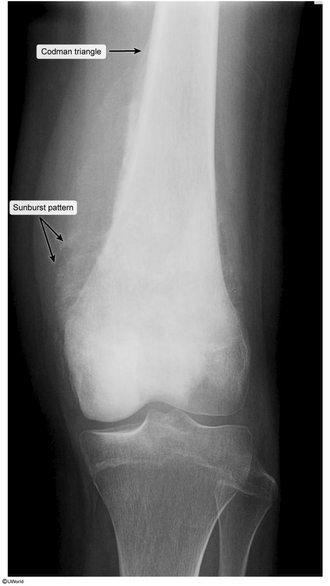

osteosarcoma

12yo girl with thigh pain for 2 months, worsening in past 10 days with a low fever for 1 week. what is it and what is the most consistent natural history of this disease?

osteosarcoma, metastasis to the lungs. high mortality rate, even with surgical resection, because small undetectable cells may have already metastasized.